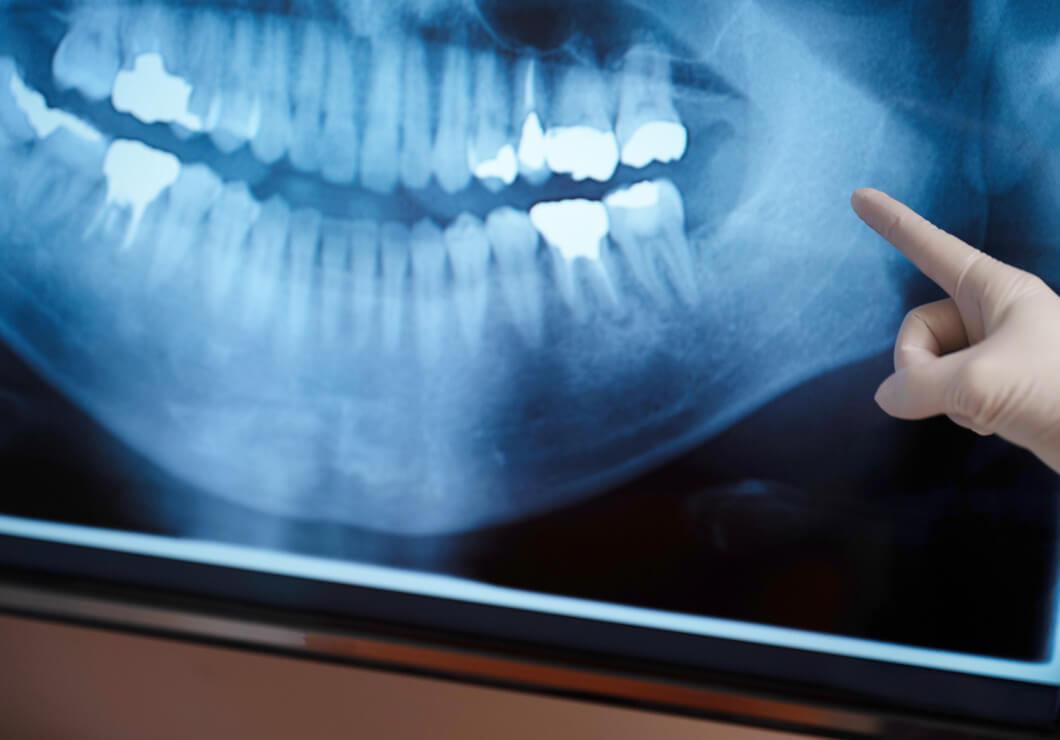

歯周病

• 歯ぐきが腫れてきた

• 歯を磨くと血が出る

• 歯がグラグラする

歯周病は、歯を支える組織や骨に炎症が起こる病気です。進行すると、顎の骨が少しずつ溶けていき、最終的には歯が抜けてしまうこともあります。

歯周病治療には、定期的な歯科検診やクリーニングに加え、毎日の丁寧な歯磨きを習慣づけることが欠かせません。

さらに、歯周病はお口の中だけでなく、誤嚥性肺炎や糖尿病など、全身の健康とも深く関わっています。

日本では50代の約8割が歯周病にかかっていると言われており、多くの人が気づかないうちに進行しています。歯周病は、歯ぐきの内側に細菌が入り込むことで起こります。

特に高齢の方は、いくつかの病気を抱えていたり、飲んでいる薬の影響でお口にトラブルが出ることもあります。体力の低下も、歯周病を発症しやすくする原因の一つです。このような患者さまのバックグラウンドなども考慮しながら、当院では丁寧に治療を進めていきます。